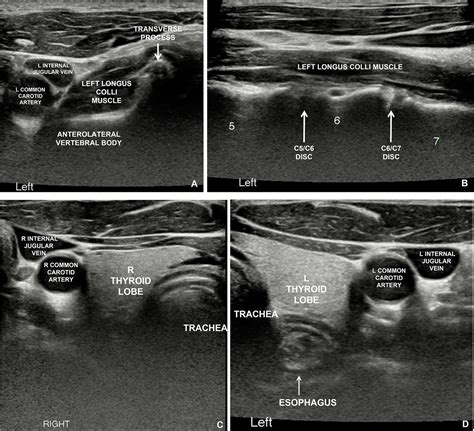

The Longus Colli muscle is a deep cervical flexor, meaning it is situated close to the bone and works to stabilize the neck rather than produce large, powerful movements like the trapezius or sternocleidomastoid. It is anatomically divided into three distinct parts: a superior oblique portion, an inferior oblique portion, and a vertical portion.

Because of its deep location, it acts as a primary stabilizer, acting much like a "corset" for the cervical spine. Its primary roles include:

• Stabilization: It supports the natural curvature of the neck, preventing the vertebrae from shifting under load.

• Cervical Flexion: It assists in nodding the head and bending the neck forward.

• Proprioception: It provides critical sensory feedback to the brain regarding the position of the neck in space.